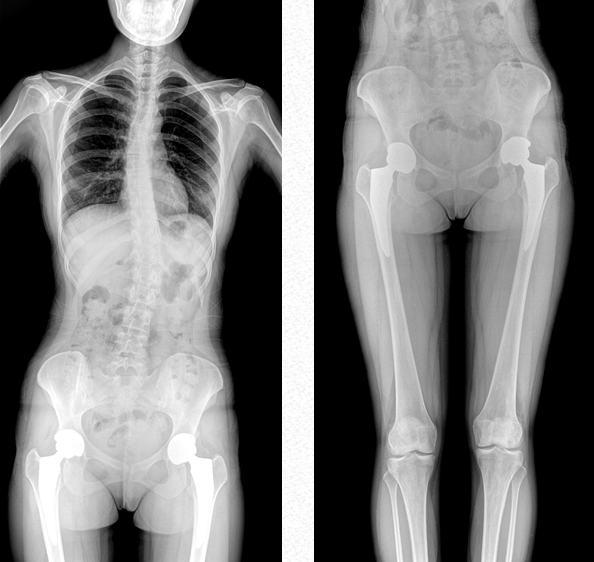

雙下肢成像

用于創傷弓|起的四肢骨折,進行較長髓內釘術前診斷、術后復診的大視野攝影。

關節運動成像

雙下肢關節運動動態攝影以及數字化動態造影等大視野臨床應用。

超大視野范圍,一次成像不拼接,減少拍片次數,縮短拍攝時間,降低患者的輻射劑量吸收

PLX8600大視野動態平板DR可攝影、可透視、可造影,臨床適用范圍廣泛,滿足臨床拍攝需求。與市面常規多張攝影再軟件拼接的DR相比,PLX8600大視野動態平板DR解決了拼接圖像存在密度不均勻,拼接處圖像配準和放大效應等問題,一體式的機架,擺位簡單快捷 ,具有畸變率低、測量精度高、圖像質量好、無拼接痕跡等優點。這款DR不僅融合了市面上17*17英寸動態DR的功能,除此之外它獨具特色的17*34英寸超大動態視野范圍,給臨床應用帶來較高價值,減輕醫院設備投入成本,獲得更大收益。